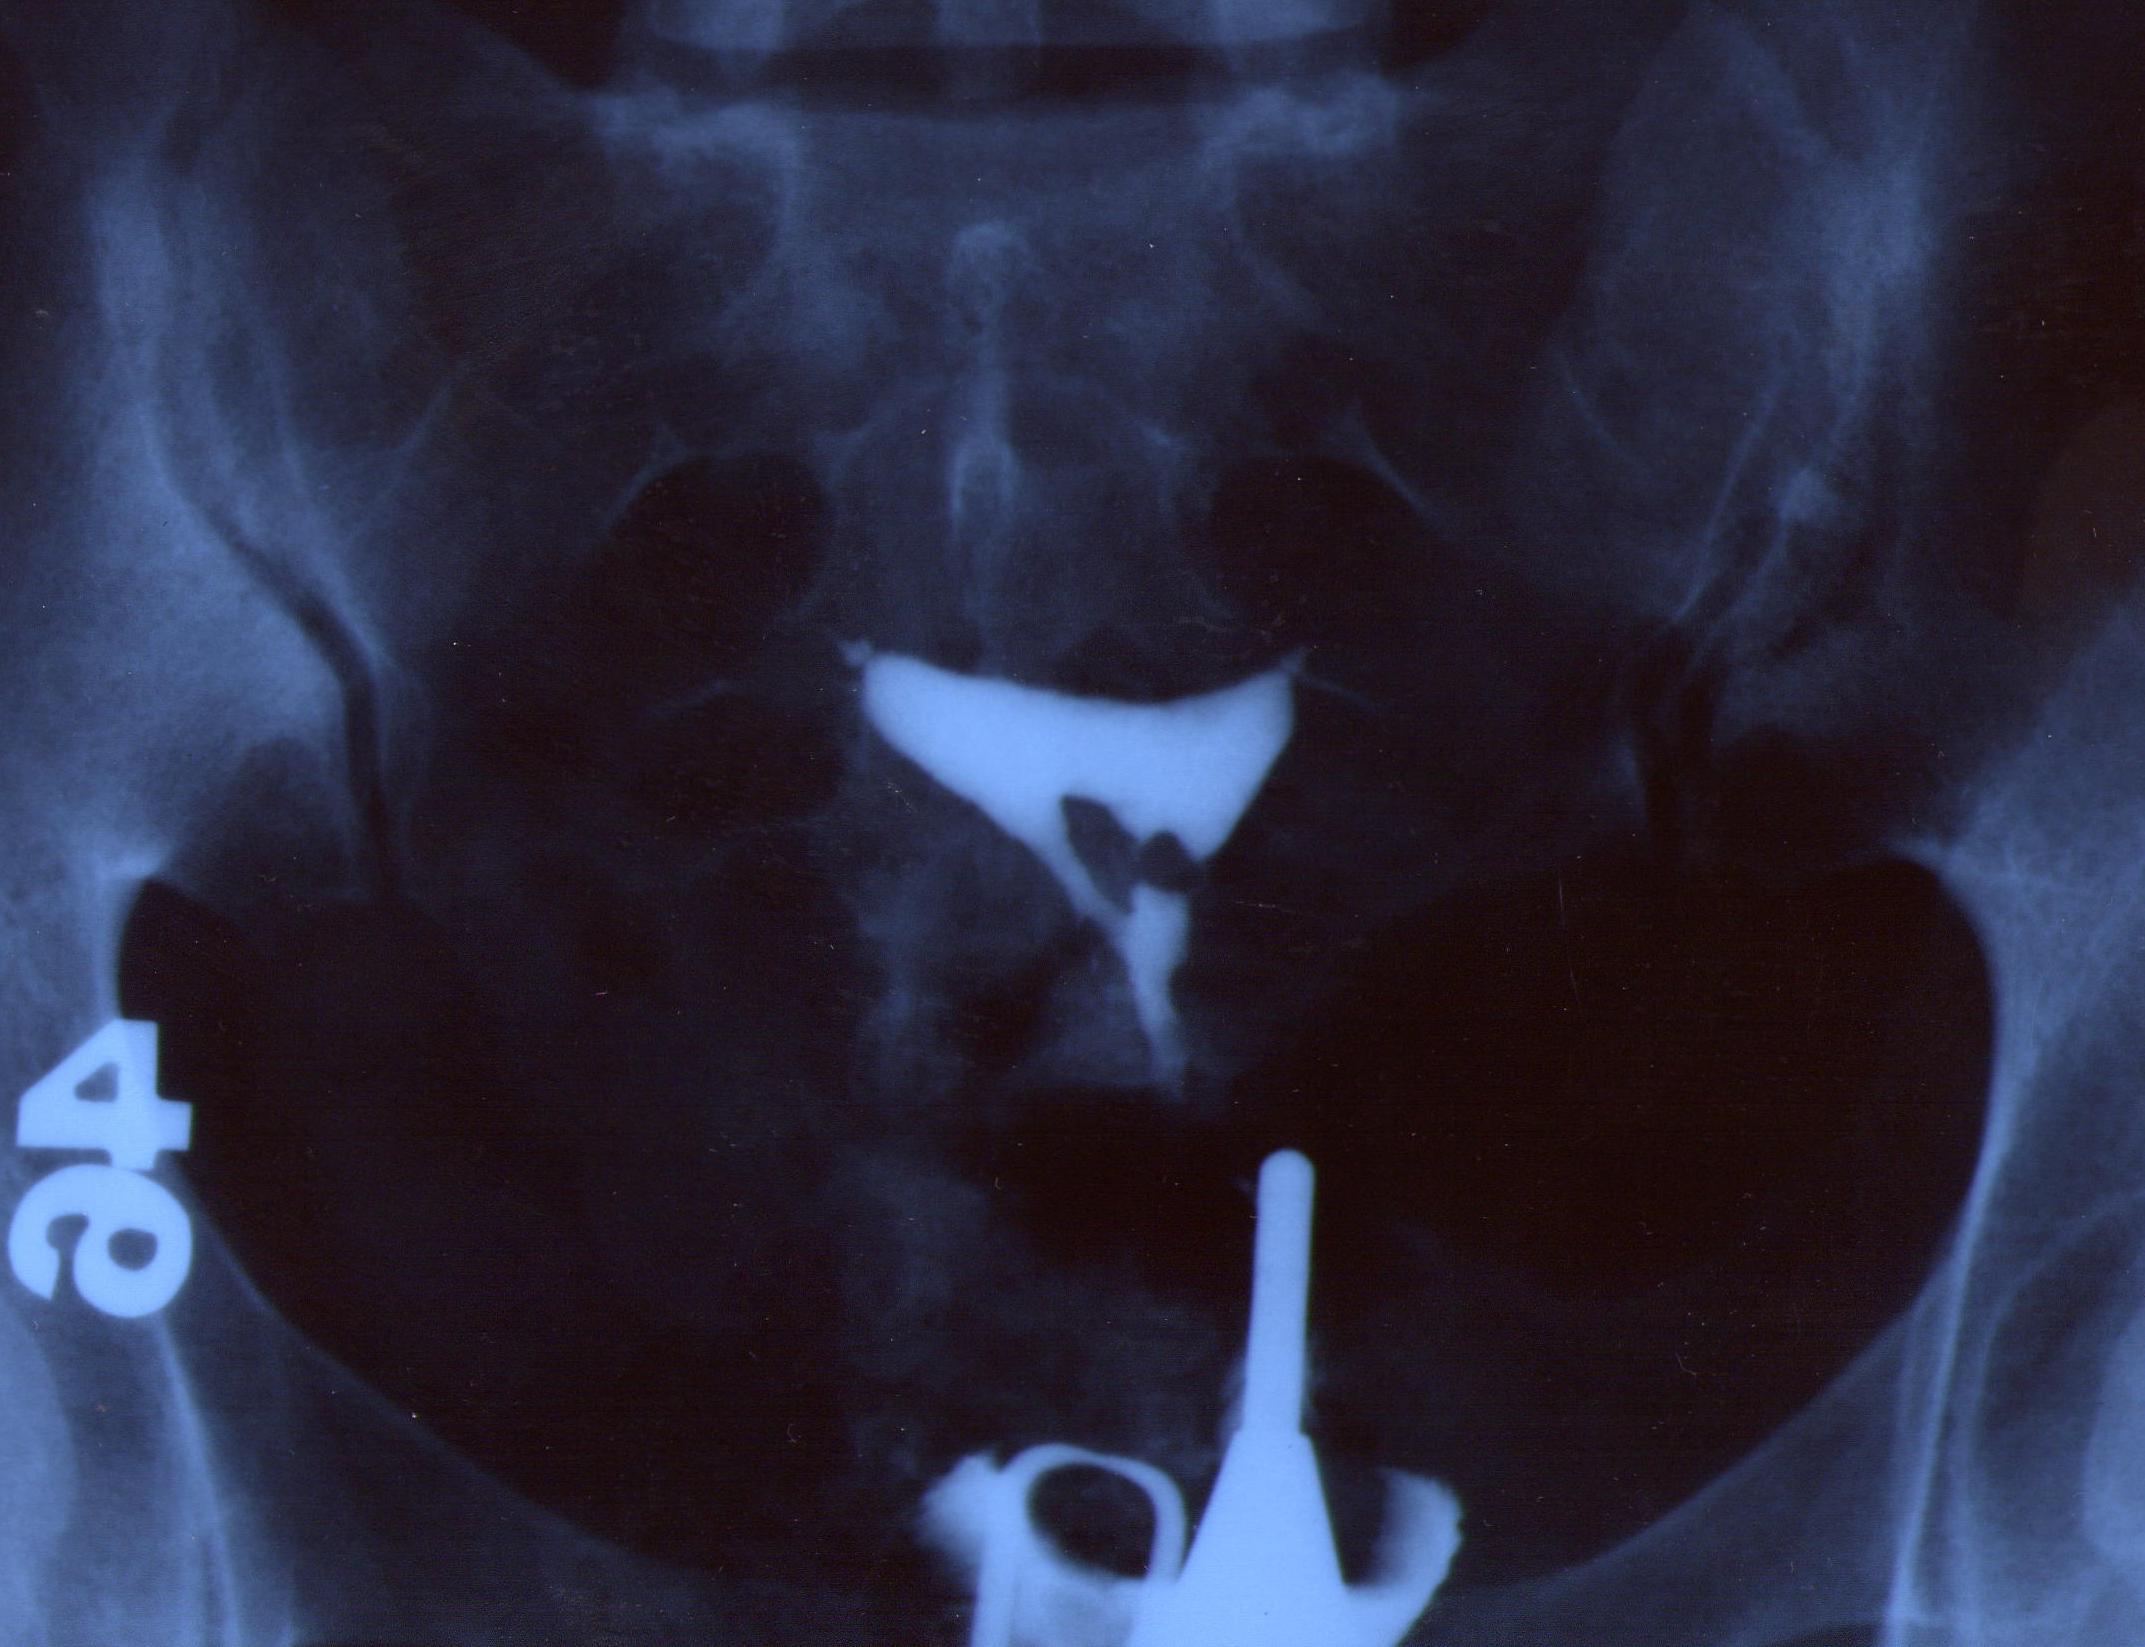

Rahim filmi, rahim boşluğu, tüpler ve karın boşluğunun alt bölümünü incelemek için çekilen özel bir röntgen filmidir. “HSG” kısaltması “rahim ve tüp filmi” anlamına gelen “Histero-Salpingo-Grafi” kelimelerinin baş harfleridir.

Bu inceleme eski veya yeni, analog veya dijital her türlü röntgen cihazıyla yapılabilir. İyonik veya non-iyonik, su bazlı veya yağ bazlı, ucuz veya pahalı iyotlu kontrast maddelerin hepsiyle de yapılabilir. İlacı (kontrast madde) rahim boşluğuna doldurabilmek için çelik, plastik veya yumuşak maddelerden yapılmış çeşitli kanüller veya sondalardan birisi kullanılabilir.

Rahim filmini uygun pozda çekmenin de iki yolu vardır: Ya rahim çengelli alet ile tutulup çekilerek uygun pozu vermesi sağlanır ya da filmi çeken makine “C” kollu ise makine rahim karşısında uygun olan açıya getirilir ve rahmi itip çekmeye ihtiyaç kalmaz.

Ağrısız rahim filmi tekniğinde hasta röntgen masasına sırtüstü yatar. Halk arasında “çatal” adı verilen bacak dayama kolları kullanılmaz. İnceleme için yeterli olabilecek, mümkün olan en küçük muayene aleti vajinaya yerleştirilir. Gerekli dezenfeksiyon işleminden sonra rahim ağzına ince ve yumuşak bir borucuk yerleştirilerek yaklaşık 10 cc (iki yemek kaşığı hacmi kadar) kontrast madde rahim boşluğu ve tüplere doldurulur. Bu sırada ilacın ilerleyişi floroskopi ekranında izlenir ve uygun pozlarda filmler kaydedilir. İnceleme sırasında iğne kullanılmaz. Batıcı, sıkıştırıcı, can yakıcı herhangi bir alet de kullanılmaz. Kontrast madde, içerisinde erimiş iyot tuzu bulunan sudur. Can yakıcı değildir. İçeri verilen bu ilacın bir kısmı inceleme bitince dışarı boşalır. Vücut içinde kalan kısmı ise birkaç saat içinde hemen hemen tamamen idrar yoluyla vücuttan atılır.

1- Nasıl ki bir vesikalık fotoğraf insanın yüzünün tam karşısından çekilmesi gerekiyorsa, rahim filmi görüntüleri de rahmin ön yüzü veya arka yüzünün tam karşısından çekilmiş olmalıdır. Aksi takdirde rahmin doğumsal anomalileri, rahim içindeki polip, myom veya yapışıklık gibi problemler görülemeyebilir.

2- Alınan filmlerde tüplerin içindeki mukoza kabartılarının iyi görülebilmesi, gerektiğinde tüp kıvrımlarının çeşitli açılardan görüntülenmesi gerekir.

1- Nasıl ki bir vesikalık fotoğraf insanın yüzünün tam karşısından çekilmesi gerekiyorsa, rahim filmi görüntüleri de rahmin ön yüzü veya arka yüzünün tam karşısından çekilmiş olmalıdır. Aksi takdirde rahmin doğumsal anomalileri, rahim içindeki polip, myom veya yapışıklık gibi problemler görülemeyebilir.

2- Alınan filmlerde tüplerin içindeki mukoza kabartılarının iyi görülebilmesi, gerektiğinde tüp kıvrımlarının çeşitli açılardan görüntülenmesi gerekir.